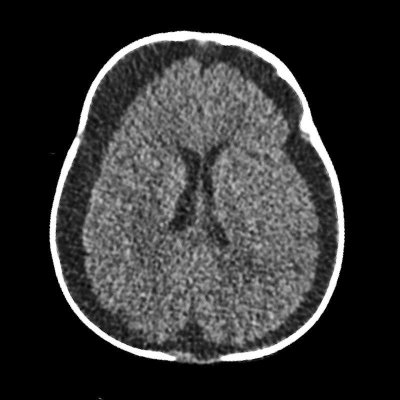

- A) Bilateral serebral konveksitede subdural higroma

- B) Kemik pencerede frontal kemikte sağda nondeplase kırık

- C) Süturlarda ayrışma

Görüntüleme Bulguları

- İstismara bağlı kafa travmasında en sık saptanan radyolojik bulgular:

- Subdural hematom: En sık görülen radyolojik bulgudur, vakaların %83-90’ında saptanır. Genellikle bilateraldir ve farklı yaşlarda hemorajik elemanlar içerir.

- Subaraknoid kanama: Hastaların yaklaşık %30’unda saptanır. En sık frontal, parietal ve temporal bölgelerde görülür ve sıklıkla birden fazla bölgeyi ilgilendirir.

- Kalvaryal kırıklar: Tek başına istismar ilişkili kafa travması açısından spesifik olmasa da çoklu kırıklar istismara bağlı travma şüphesini artırır.